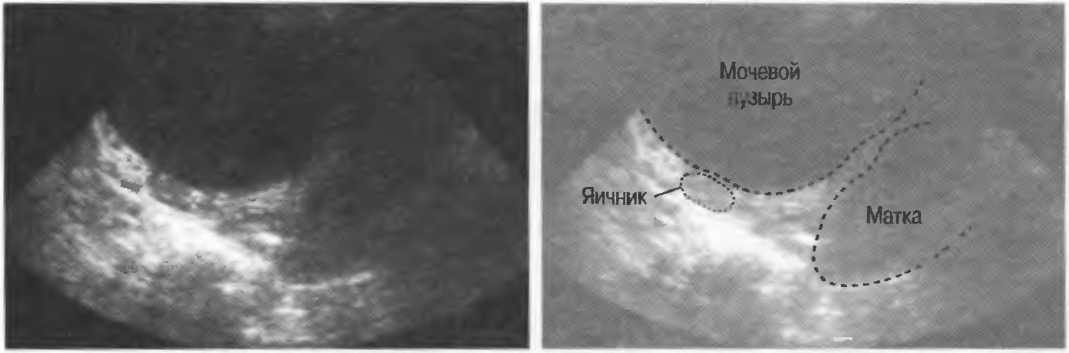

Газ отражает ультразвук и экранирует ткани, расположенные сзади, в результате преломления и акустической тени от газа. Газ в кишечнике может экранировать печень, поджелудочную железу, парааортальные лимфоузлы, матку, яичники. Иногда удается сместить газ в кишечнике, например при наличии наполнения мочевого пузыря матка и яичники почти всегда легко визуализируются, так как кишечные петли «убраны» из поля зрения. В других случаях бывает необходимо делать косые, латеральные или дорсальные сканы в положении пациента стоя или сидя (рис. 19).